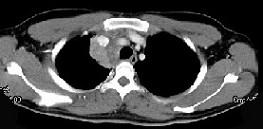

问题 男,21岁,干咳,盗汗一月伴消瘦,CT如图,应先考虑为 ( )

选项 A、右上肺上沟瘤 B、右上肺不张 C、纵隔型肺癌并纵隔淋巴结核转移 D、淋巴瘤 E、右上肺结核并纵隔淋巴结核

答案 E